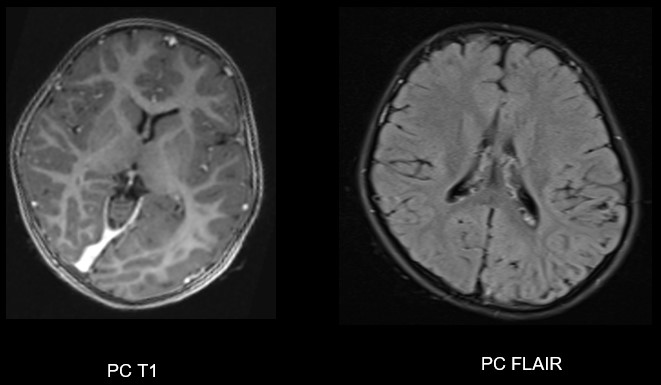

A. FINDINGS: MRI BRAIN WITH IV CONTRAST

• C. No volume loss in bilateral cerebellar hemispheres. No abnormal post-contrast enhancement.

Left posterior quadrantic dysplasia with associated subcortical white matter signal abnormalities and periventricular nodular heterotropia.